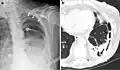

Radiografia de tórax (esquerda) e tomografia computadorizada (direita) demonstrando fibrotórax -

O diagnóstico de fibrotórax é normalmente feito por meio de um histórico médico adequado, combinado com o uso de técnicas de imagem apropriadas, como radiografia simples de tórax ou tomografia computadorizada.[3] Essas técnicas de imagem podem detectar o fibrotórax e o espessamento pleural que envolve os pulmões.[7] A presença de uma casca espessada com ou sem calcificação é uma característica comum do fibrotórax quando a imagem é obtida.[3] As tomografias computadorizadas podem diferenciar mais prontamente se o espessamento pleural se deve à deposição de gordura extra ou ao verdadeiro espessamento pleural do que os raios-x.[3]

Se o fibrotórax for grave, o espessamento pode restringir o pulmão do lado afetado, causando perda de volume pulmonar.[7] Além disso, o mediastino pode ser fisicamente deslocado para o lado afetado.[3] Uma redução no tamanho de um lado do tórax (hemitórax) em uma radiografia ou tomografia computadorizada do tórax sugere cicatrização crônica.[6] Sinais da doença subjacente que causa o fibrotórax também são ocasionalmente observados na radiografia.[6] A tomografia computadorizada pode mostrar características semelhantes às observadas em uma radiografia simples.[7] O teste de função pulmonar demonstra normalmente achados consistentes com doença pulmonar restritiva.[6]